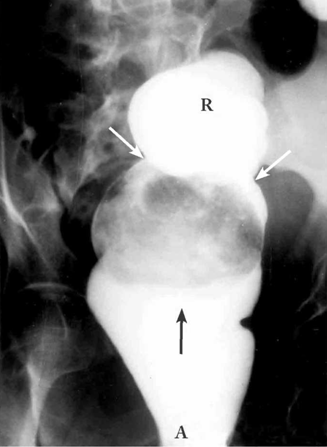

חוקן בריום - בחוקן בריום ניתן לראות חסימה של המעבר או היצרות קשה של הכרכשת בגובה החסימה. לעתים אפשר להדגים פקלומה (Fecaloma) בחלחולת (תצלום 7.6).